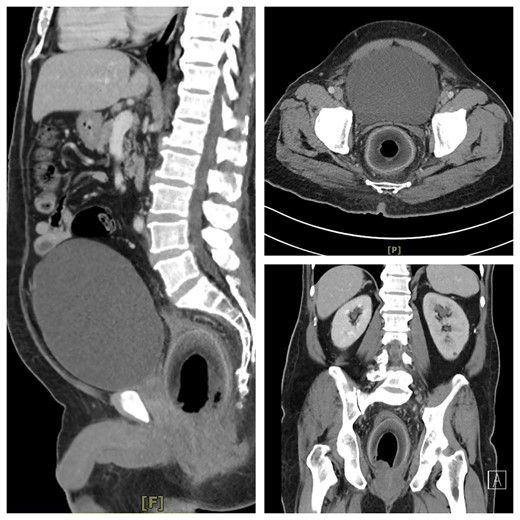

Dokter kemudian melakukan CT Scan dan terlihat buah kelapa tersangkut di rektumnya, yang menekan uretra dan membuatnya sulit buang air kecil. Dalam laporannya, petugas medis tidak mengungkap tanggal kejadian dan identitas pasien, selain data usia.

Kelapa di rektum Foto: British Journal of Surgery |

Upaya dokter berhasil dengan aman mengeluarkan kelapa berukuran 7,5cm x 5,7cm dari rongga perutnya dan mengeluarkan 2.000ml urine yang menumpuk selama dua hari.